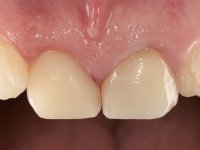

The final result presented an aesthetically integration that has been achieved with a less invasive approach.